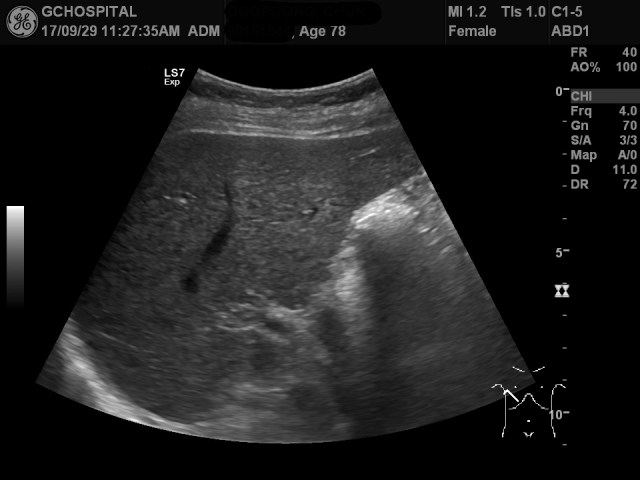

그런데, 간 우엽의 지붕부위는 제대로 확인하지 못한 부분이 존재합니다. 위 영상이 간의 지붕부위를 찍은 영상이지만, 지붕부위의 일부분이 잘려있습니다. 누워있는 자세와 좌측 측와위자세에서 시도해봤지만, 이보다 위쪽을 보는데 어려움이 있었습니다.

원래 초음파영상을 시행하기 전부터 해당 병변이 있다는 사실을 알고 있었음에도 간내석회화나 간낭종 여부를 확인하는게 어려웠던 겁니다.